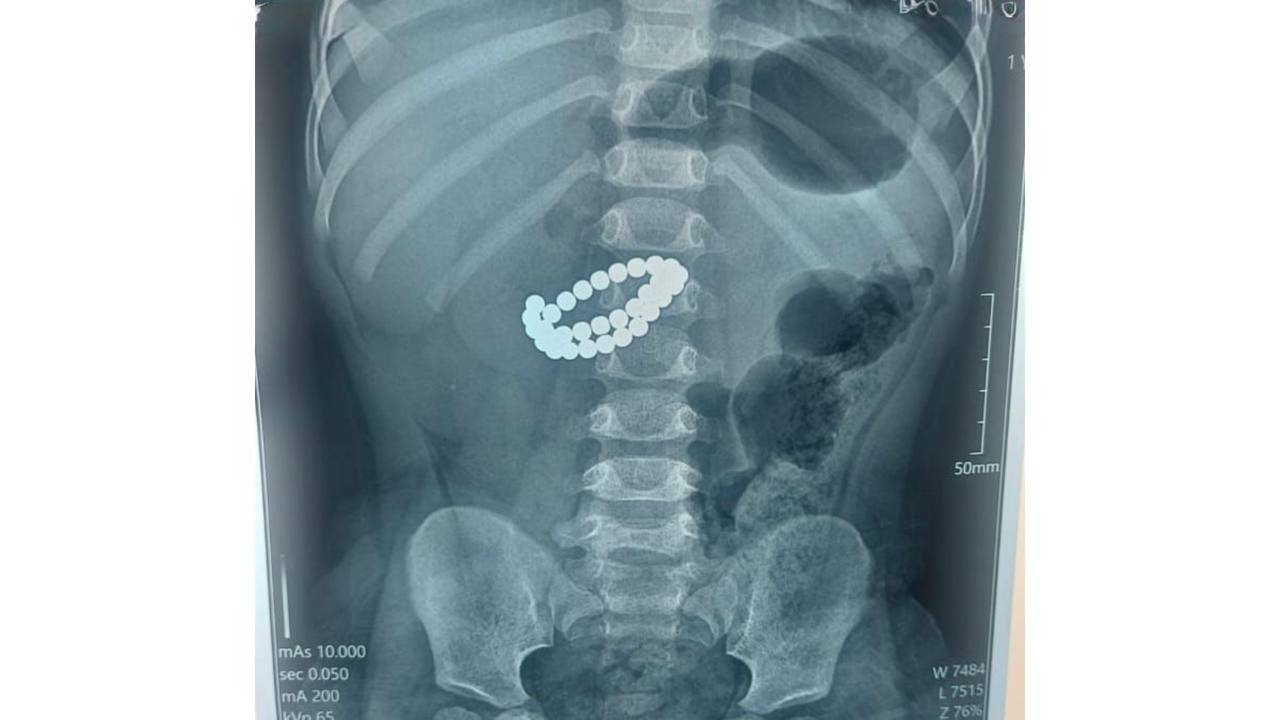

Қабылдау бөліміне 1 жас 9 айлық бала өте ауыр жағдайда жеткізілген. Тексеру нәтижесінде дәрігерлер “ішектегі бөгде заттар – 31 магнит, жіңішке ішектің көп жерден тесілуі, перитонит” диагнозын қойды.

Баланың өмірін сақтап қалудың жалғыз жолы – шұғыл хирургиялық ота жасау еді. Дәрігерлер ортаңғы лапаротомия жасап, құрсақ қуысы ағзаларына толық тексеру жүргізді. Ота барысында магниттер ішектен алынып, жіңішке ішектегі көптеген тесік тігілді, құрсақ қуысы тазартылып, дренаж орнатылды. Сонымен қатар ішекке трансаналдық интубация жасалды.

Орталық хирургі Асқар Ризвановтың айтуынша, магниттердің басты қаупі – олардың ағзаға бөлек-бөлек түскенімен, ішекте бір-біріне тартылып, ішек қабырғасын қысып қалуында.

“Магниттердің арасында ішек қабырғасы қысылады, қан айналымы бұзылады, тіндер жансызданады, тесік пайда болады. Соның салдарынан санаулы сағаттардың ішінде перитонит дамуы мүмкін. Ата-аналар көбіне баланың жағдайы қаншалықты жылдам нашарлайтынын аңғармай қалады”, – дейді хирург.